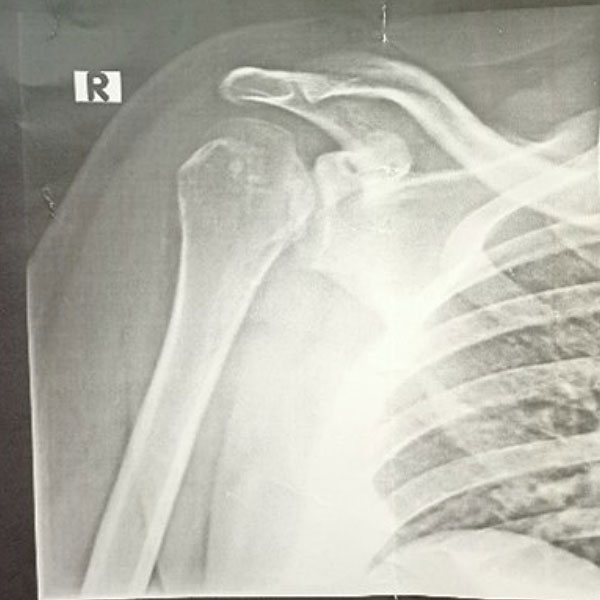

Initially, the patient had presented to an emergency room, where he had stated that his pain was the result of his friend having gently pulled his shoulder while joking around. Upon a subsequent X-ray (fig. 1) the patient had been diagnosed with a shoulder contusion.

Subsequent CT and MRI scans provided clarity: the shoulder contusion had been a misdiagnosis. Instead, the patient suffered from a locked posterior shoulder dislocation. The locking occurred between an anterior defect in the humeral head, known as a reverse Hill-Sachs lesion, and the posterior glenoid rim.